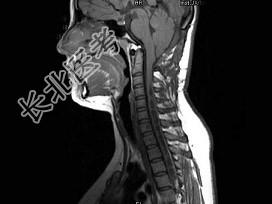

- 单项选择题女,16岁, 四肢活动不利半年,走路不稳2个月, MRI检查,最可能的诊断为 ( )

C、Chiari畸形(Ⅰ型)并脊髓空洞形成